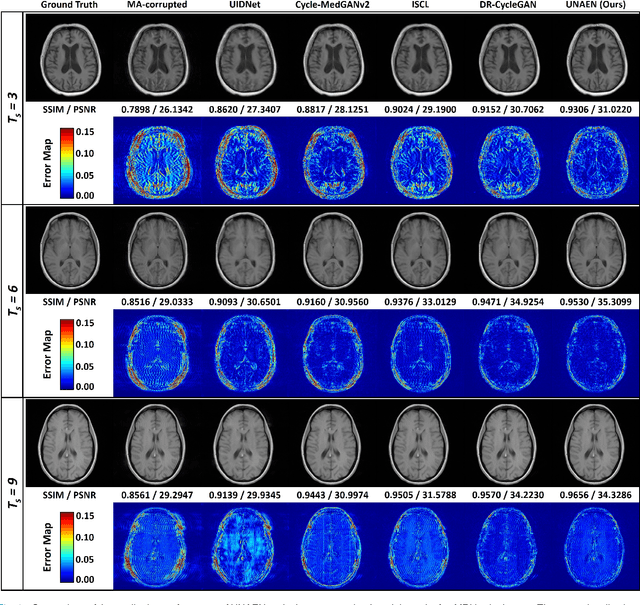

Abstract:Motion artifact reduction is one of the most concerned problems in magnetic resonance imaging. As a promising solution, deep learning-based methods have been widely investigated for artifact reduction tasks in MRI. As a retrospective processing method, neural network does not cost additional acquisition time or require new acquisition equipment, and seems to work better than traditional artifact reduction methods. In the previous study, training such models require the paired motion-corrupted and motion-free MR images. However, it is extremely tough or even impossible to obtain these images in reality because patients have difficulty in maintaining the same state during two image acquisition, which makes the training in a supervised manner impractical. In this work, we proposed a new unsupervised abnomality extraction network (UNAEN) to alleviate this problem. Our network realizes the transition from artifact domain to motion-free domain by processing the abnormal information introduced by artifact in unpaired MR images. Different from directly generating artifact reduction results from motion-corrupted MR images, we adopted the strategy of abnomality extraction to indirectly correct the impact of artifact in MR images by learning the deep features. Experimental results show that our method is superior to state-of-the-art networks and can potentially be applied in real clinical settings.